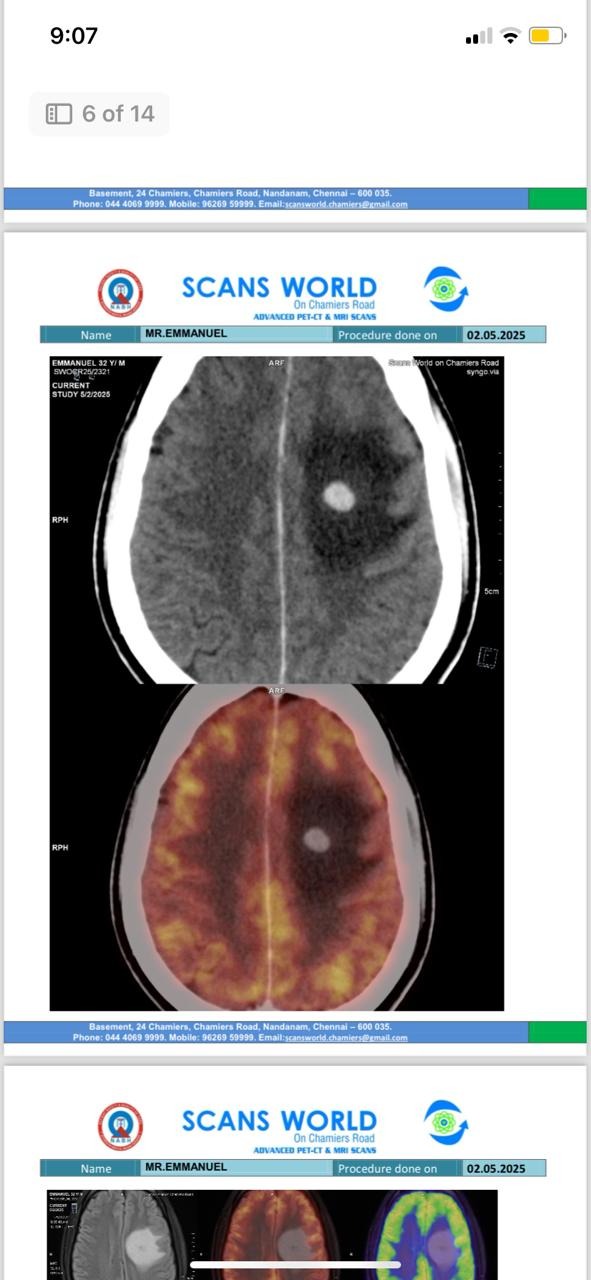

Manny was diagnosed with stage 4 clear cell renal cell carcinoma.

The cancer had come back—not only in the only kidney he has left, but also in the very space where his removed kidney once was.

And worse—it had already spread to his lungs, brain, and lymph nodes.

Doctors have confirmed this is an aggressive, recurring, metastatic cancer.

He needs urgent immunotherapy and targeted radiation for his brain lesion.

We recently received the results of his latest PET-CT scan, and we are grateful to share some encouraging news. The doctor described the results as very encouraging. The scan shows a further reduction in the size and activity of the tumor in his remaining kidney. The lesions in his lungs have continued to shrink, and there is no evidence of any new active disease elsewhere in his body. The brain lesion that was treated has remained stable, and several affected lymph nodes have shown continued improvement.